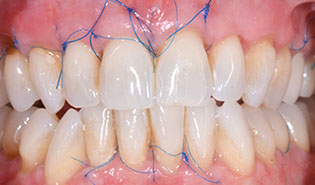

3.3 FASTP (Fibrin Assisted Soft Tissue Promotion Technique Plastic)

Aesthetic Surgery for the Treatment of Muco-Gingival Recession

One of the most common findings in the population is gingival recession.

Amongst 60 year olds, 90% have at least 1 tooth with 1mm recession and 40% presenting multiple sites with >3mm recession. There is an increasing need to treat gingival recession defects in the population or to improve the biotype of gingival tissue.

There are several treatment options available to correct muco-gingival recession. The use of a tunneling technique and autologous fibrin is a valuable adjunct to help patients with Millers Class 1 and Class 2 recession are presented and demonstrated.

Understanding the FASTP treatment of Millers Class 1 and Class 2 recession defects

Correction of Millers Class 1 and Class 2 defects

Learn the necessary surgical tunnelling, tissue release, graft placement, graft stabilization and novel suturing techniques